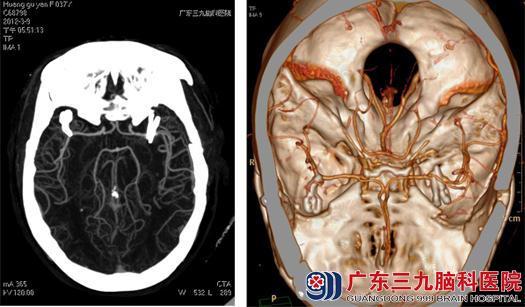

入院第二天,黄女士顺利接受了双侧动脉瘤夹闭术,术中双侧开颅,吾太华主任很顺利地找到了导致黄女士头痛头晕、颅内出血的“元凶”,并在电生理监测下分别夹闭双侧动脉瘤。术程顺利,出血不多,术后予以缓解血管痉挛、止血、补液等治疗。两个星期后,黄女士康复出院。

术后CTA